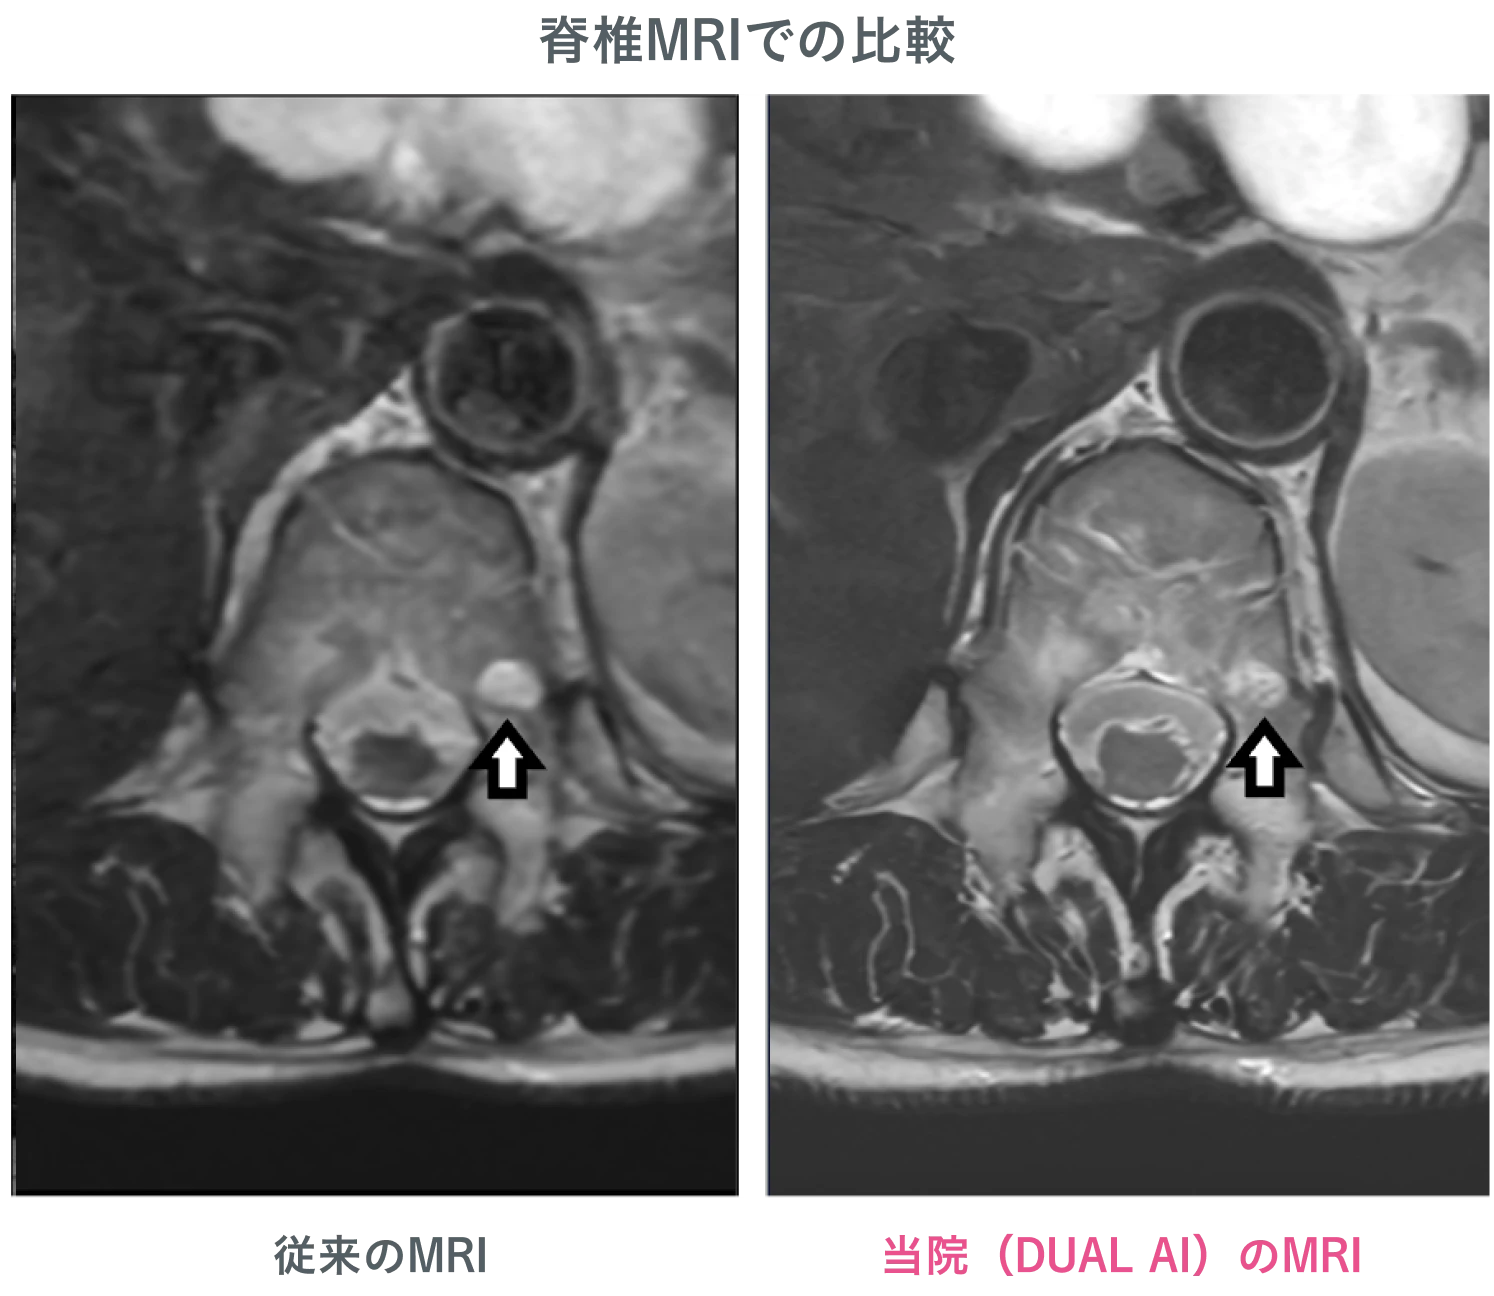

AI を搭載した最新鋭MRI・CTを導入

医療技術の進化を取り入れ、高精度な検査を実現。AI による画像解析により、見落としのリスクを最小限に抑えます。

高原クリニック イノベーティブスキャンのMRIは、すい臓がんの早期発見において高精度な診断を実現しています。